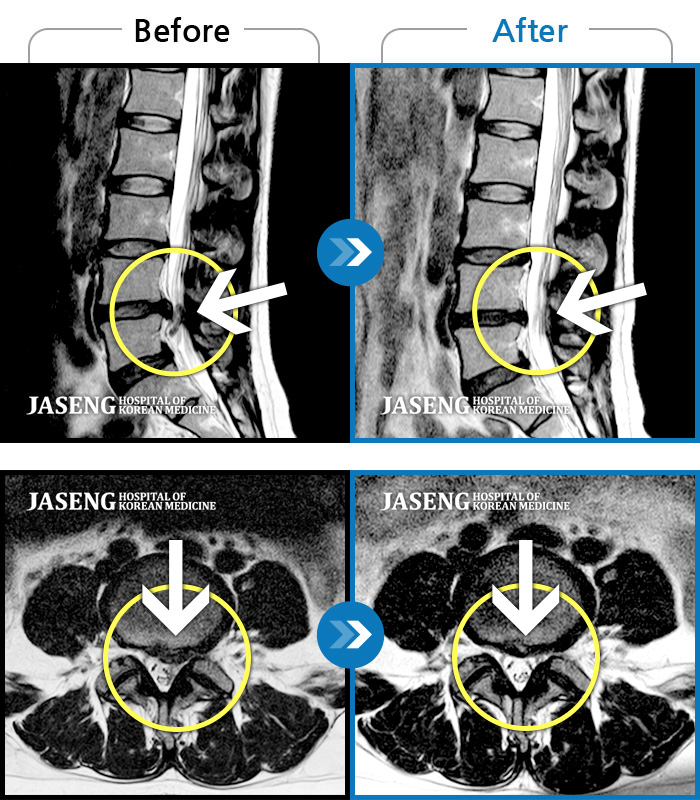

MRI ũ ʸ Ȯϼ.

ȯںп Ǹ ǿ ԿǾ, ο ġ ۿ Ƿ ġḦ Ͻñ ٶϴ.